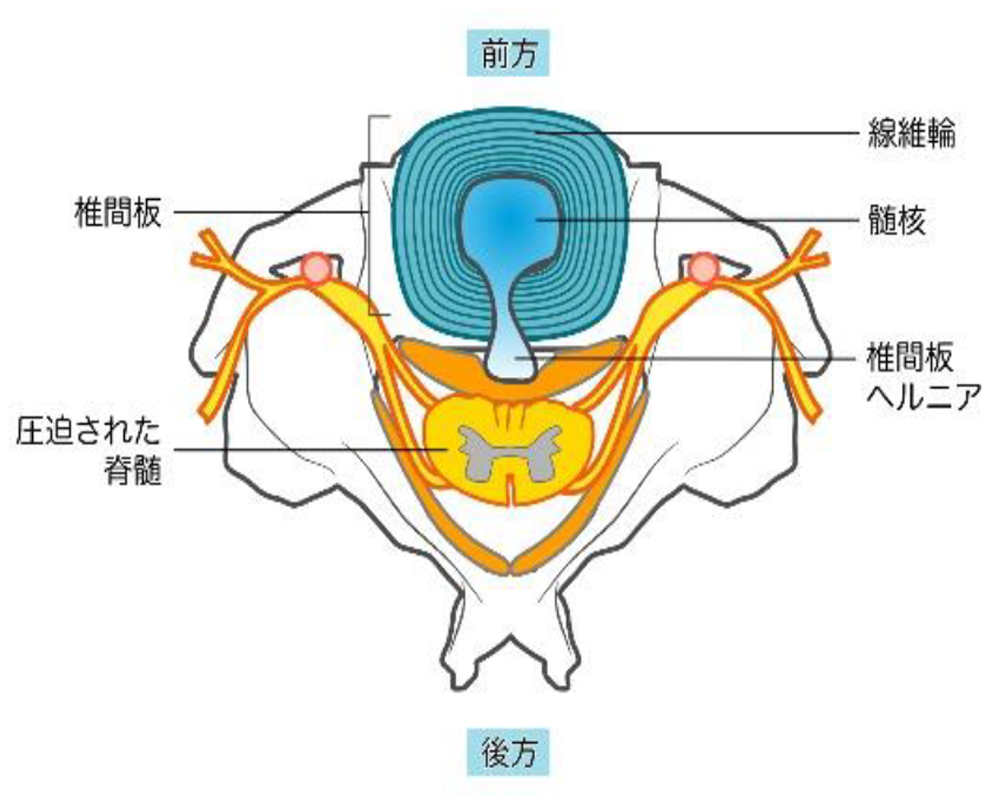

■頸椎椎間板ヘルニア

頸椎を構成する椎骨と椎骨の間には椎間板というクッション性のある組織が存在します。何らかの原因でその椎間板が飛び出し、神経を圧迫するのが椎間板ヘルニアです。

-

(症状)

- 腕や手の痛み、シビレ

- 握力の低下、脱力感

- 手のむくみ

- 腕から手の筋肉の萎縮

- 頭痛

- 耳鳴り

- めまい

- 足の痛み、突っ張り感、シビレ

- 歩行障害

- 排尿・排便障害